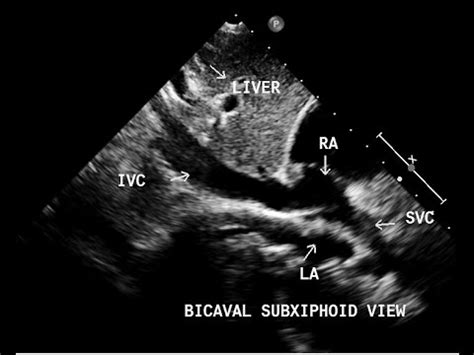

Hey guys! Ever wondered how those crystal-clear images of your heart’s big veins are captured during an echocardiogram? Well, it all boils down to the bicaval view echo probe position . This is super important for cardiologists and sonographers to accurately diagnose and understand what’s happening inside the heart. Getting this position right allows us to visualize the superior and inferior vena cava (the big veins bringing blood back to the heart) and the right atrium, giving a comprehensive view of the heart’s function. Let’s dive deep into how to nail this position and get those perfect images! This is critical for assessing right heart function, detecting issues like thrombus (blood clots), and measuring the size and function of the vena cava. Accurate probe placement is key to getting these measurements right and making sure patients get the best care.

So, why is this bicaval view so crucial? Think of the heart as a bustling city, and the vena cava are the highways bringing in all the traffic (blood) from the rest of the body. The bicaval view gives us a panoramic view of these highways as they enter the heart’s main station (the right atrium). This view is your go-to for checking the size and shape of these major vessels and how they function. This is especially vital when checking for clots, which can be deadly. It also helps in assessing the pressure within the right atrium, a key indicator of heart health. Furthermore, it gives a good look at the tricuspid valve, ensuring it’s working properly. This view is also super helpful in assessing patients with shortness of breath, chest pain or other symptoms related to heart problems, the bicaval view can provide crucial insights.

Now, let’s get into the nitty-gritty of how to get the perfect view. First, remember the patient should be lying on their left side, which is known as the left lateral decubitus position. This helps bring the heart closer to the chest wall. The probe itself is the magic wand, and the specific type you use (usually a phased array) is designed for this kind of imaging. Then comes the tricky part: the probe position. Imagine you are trying to catch the sun at the optimal angle. The goal is to position the probe under the sternum (the breastbone), aiming slightly towards the patient’s right shoulder. The idea is to align the ultrasound beam with the vena cava so you can see them clearly as they enter the right atrium. Be patient and adjust slightly until you get the best image. The orientation marker on the probe is your best friend here; it should point toward the patient’s right. It may take some practice, but you’ll get the hang of it.

Alright, let’s break down the process step-by-step for the bicaval view echo probe position . First, you’ll need the right equipment: an ultrasound machine, the right kind of probe (usually a phased array), and some acoustic gel (that stuff that makes everything glide smoothly). The patient should be positioned in the left lateral decubitus position. This positioning moves the heart closer to the chest wall, making it easier to get clear images. Now, apply the acoustic gel liberally to the probe head. This helps eliminate air pockets and ensures good contact with the skin. Place the probe just below the sternum, aiming towards the patient’s right shoulder. Gently angle the probe and try to visualize the right atrium and the vena cava. Remember to keep the probe flat against the chest wall to get the best contact and minimize any loss of image quality. Slight adjustments are often necessary to find the sweet spot, the one where the images are super clear. Scan through the various angles to see which one gives you the best picture of the superior and inferior vena cava entering the right atrium.